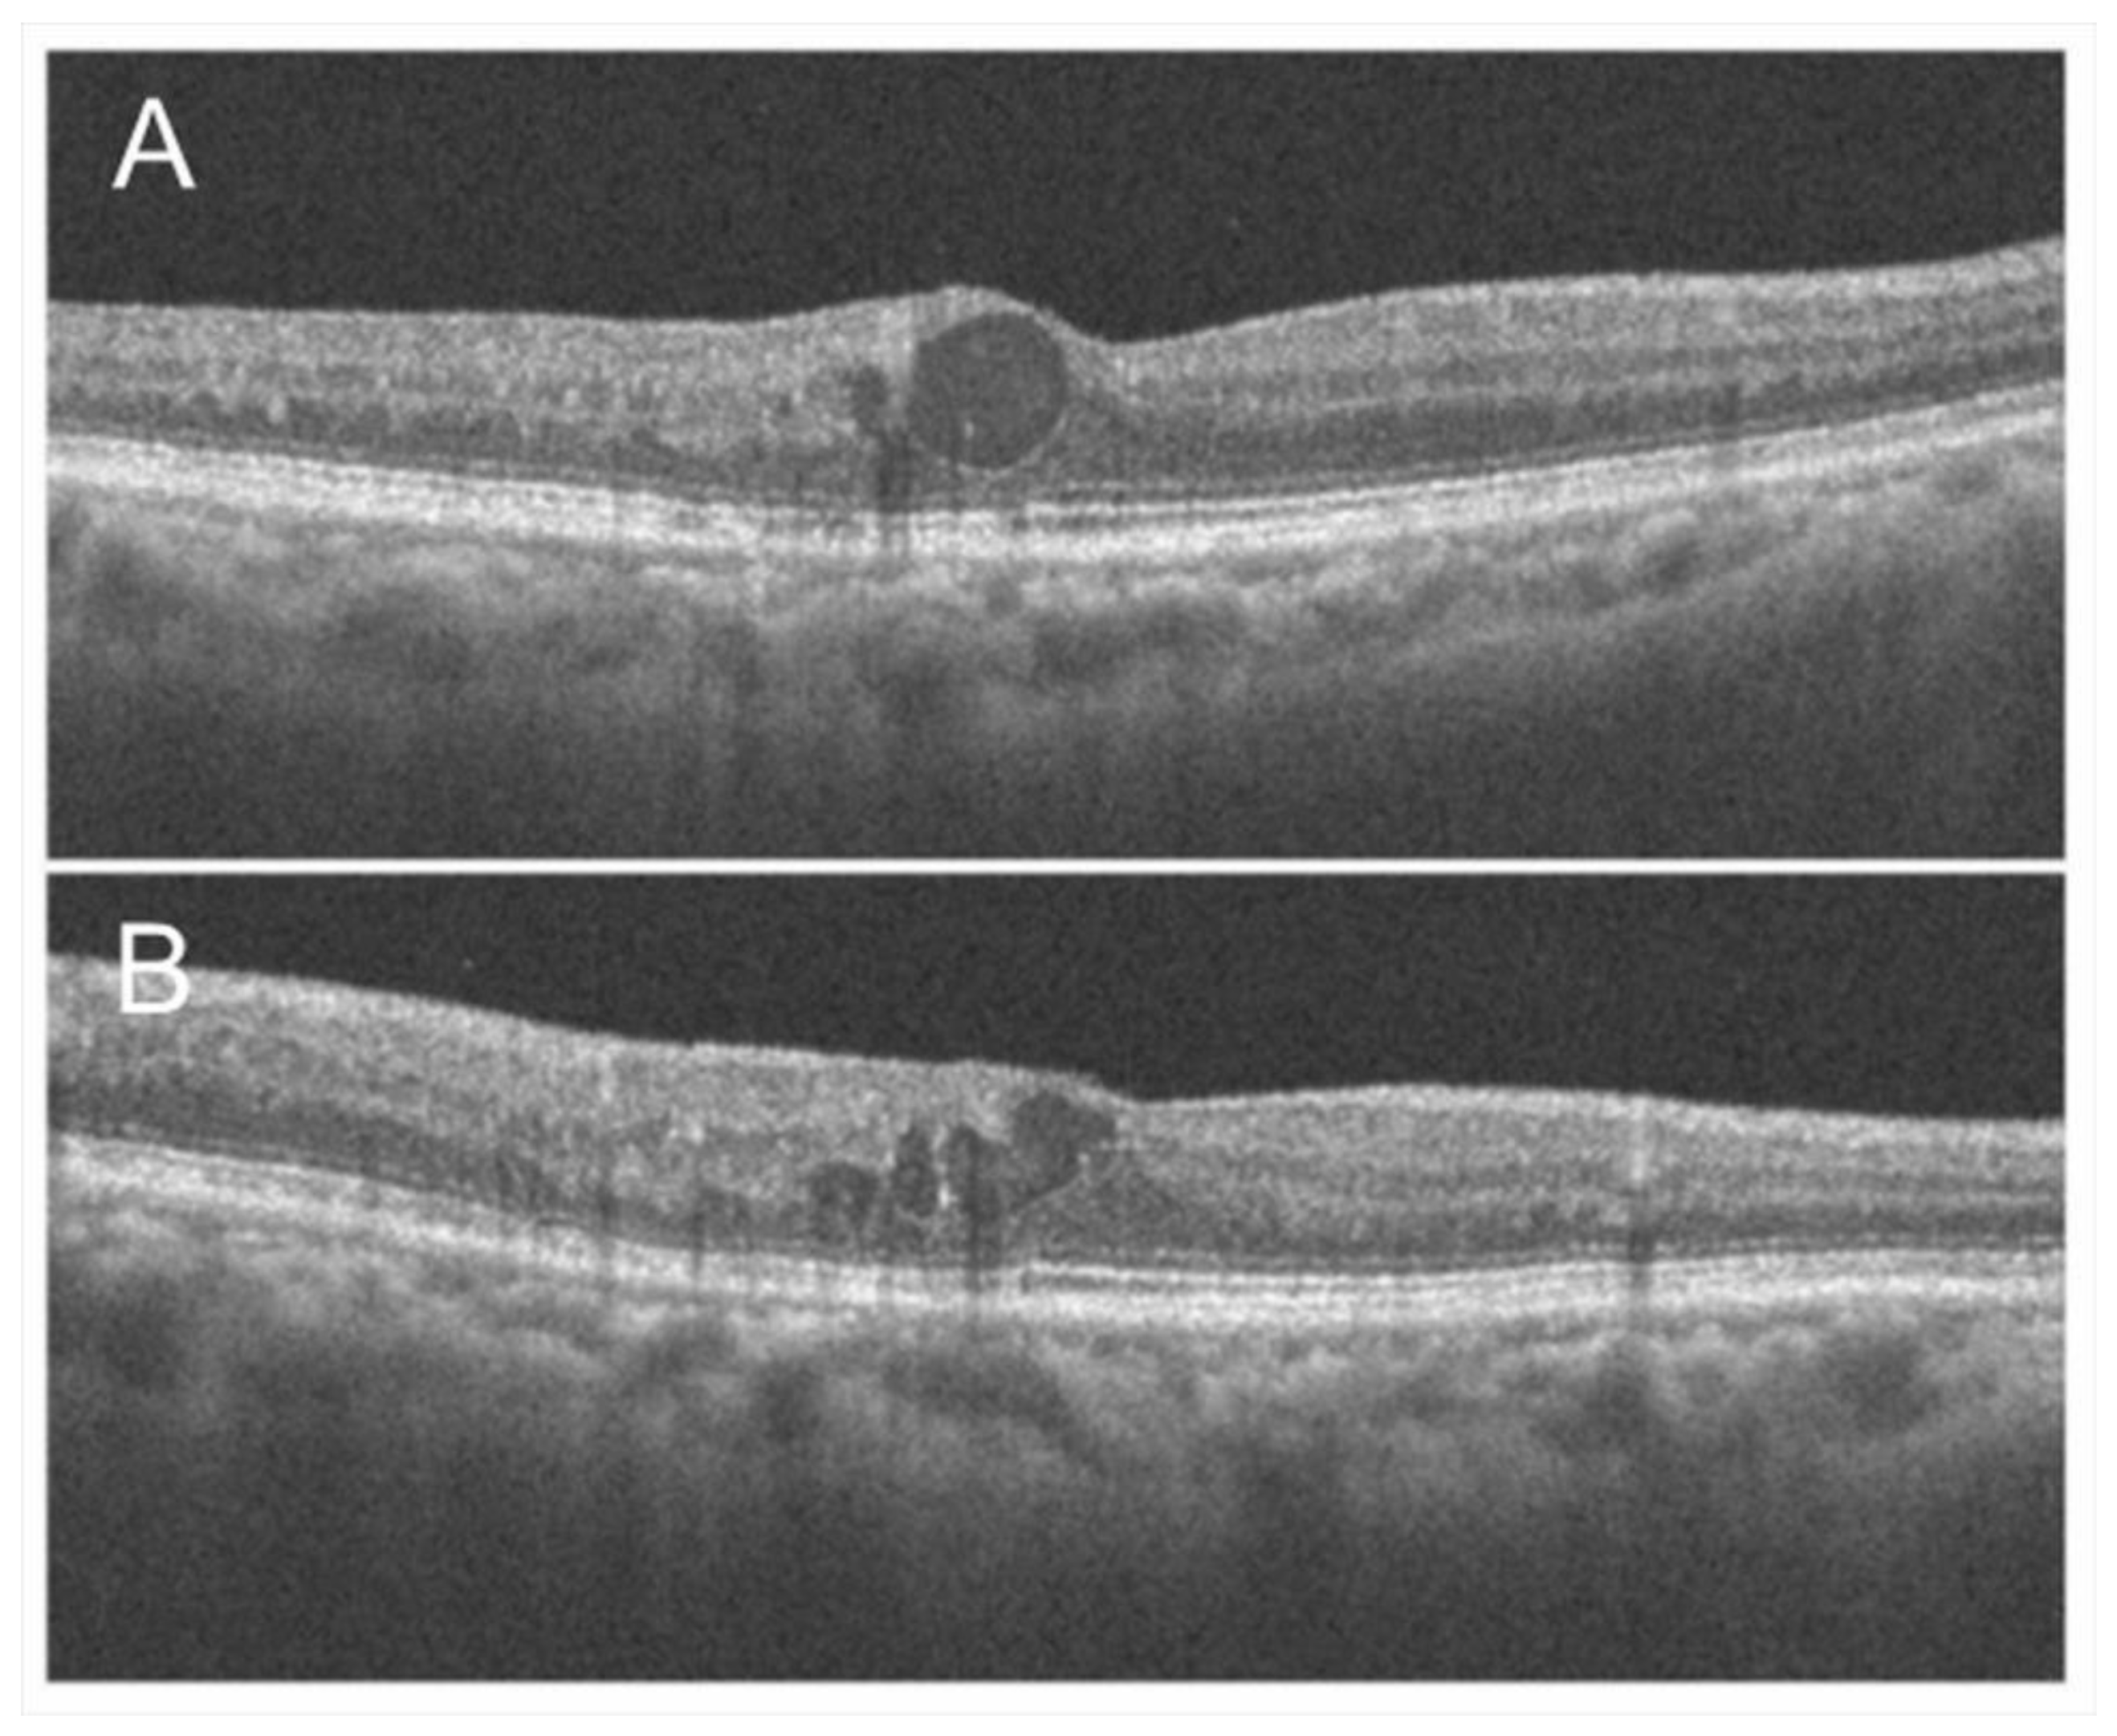

Figure 5.

Optical coherence tomography findings of chronic macular edema in an eye with branch retinal vein occlusion. (A) Horizontal scan. (B) Vertical scan. Although cystoid macula edema is observed, the foveal photoreceptors are relatively intact, and the best-corrected visual acuity was 20/16.